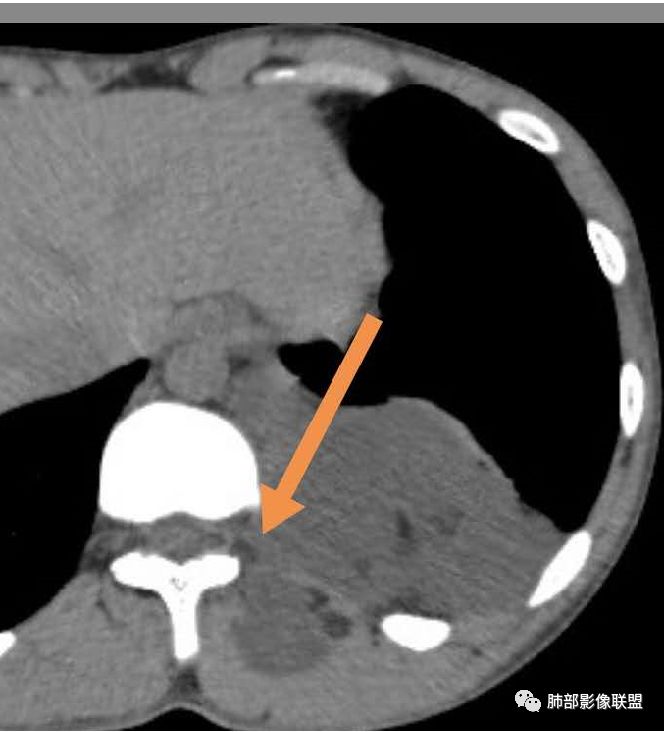

3.部位深在且四处侵入,含脂质较少或整体密度高于脂肪的脂肪类肿瘤应当想到脂肪肉瘤的可能性,因为它可以粘液样变。

但本例病灶边界清楚,有一定规模而相邻骨质未见异常,提示整体倾向良性或者恶性程度不高。

包膜钙化往往提示病灶存在时间较长且较为固定。

良性脂肪肿瘤有多种,脂肪瘤、纤维脂肪瘤、血管脂肪瘤、神经脂肪瘤、梭形细胞脂肪瘤、冬眠瘤等等……

4.冬眠瘤为含有棕色脂肪成分的脂肪瘤,又称为棕色脂肪瘤,因类似冬眠动物的冬眠腺而得名。良性,生长缓慢,好发年龄30-40岁,男性稍多。血管丰富有时会触及局部皮温相对高。